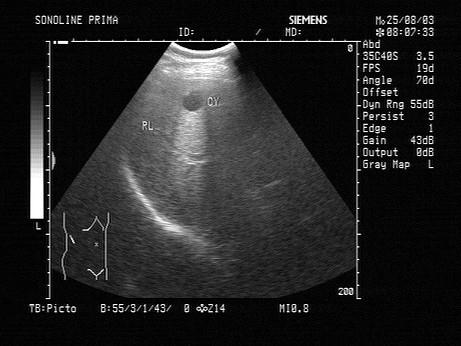

问题 肝囊肿的声像图表现,下列哪一项是错误的?(?)

选项 A.囊壁薄而光滑 B.囊壁较厚,光滑,呈双层 C.侧壁出现回声失落 D.后方回声增强 E.彩色多普勒显示囊壁处短条状血流信号

答案 B